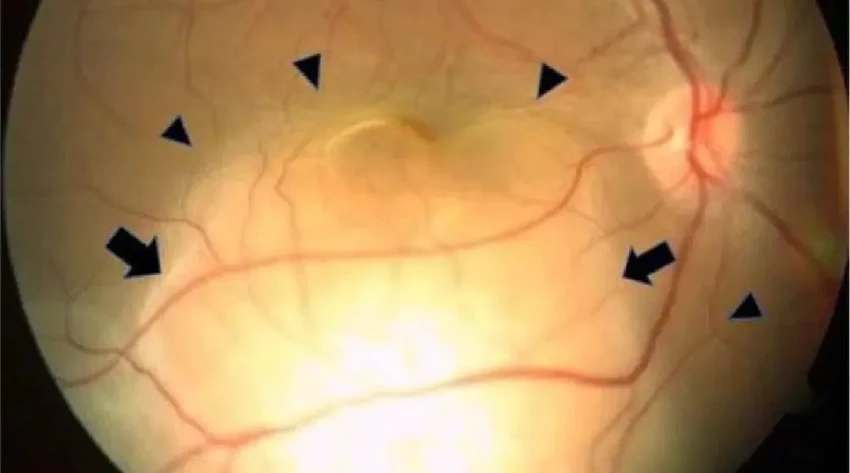

Первичный осмотр лишь углубил недоумение: глаза выглядели совершенно нормально. Но заглянув на глазное дно, офтальмологи увидели странную желтоватую массу, отслоившую сетчатку правого глаза. Похожая, но меньшая картина была и в левом. Анализы крови тоже молчали — никаких инфекций, никаких системных сбоев. Так куда же смотреть дальше?